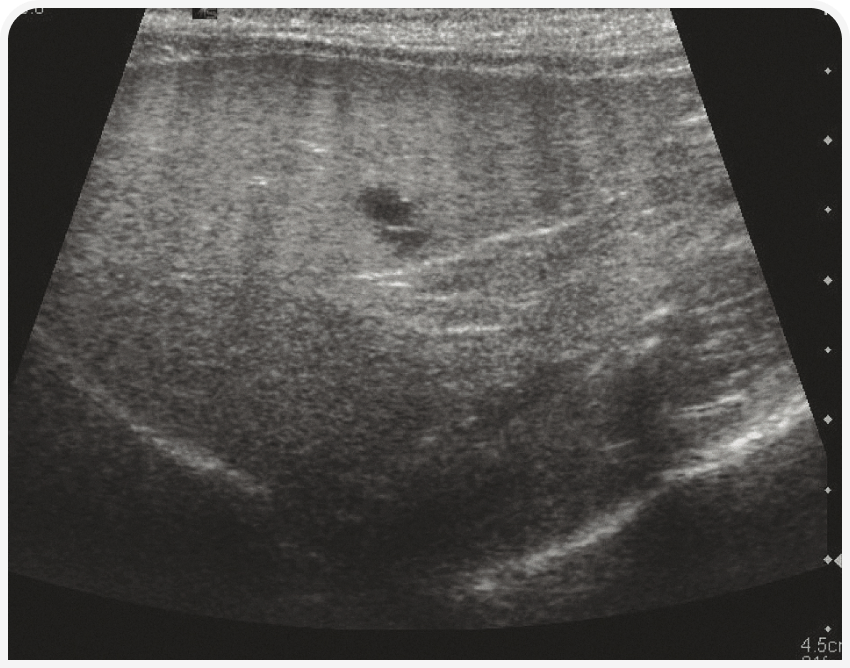

В основном при ультразвуковом исследовании можно выявить изменение размеров (чаще всего гепатомегалию) и эхогенности печени или наличие в ней узелка или объемного новообразования. Ультразвуковое исследование позволяет с высокой чувствительностью обнаруживать изменения паренхимы, но оно неспецифично, поэтому любые изменения следует интерпретировать с учетом клинических проявлений. Например, гиперэхогенную гепатомегалию на фоне желтухи у кошек можно с высокой вероятностью считать проявлением липидоза, а у собак с диабетом считать вариантом нормы. При этих двух заболеваниях паренхима печени также будет разрежена (Рисунок 4). Острый гепатит может характеризоваться гипоэхогенной гепатомегалией, а хронический – гетерогенностью тени и неровными краями печени.